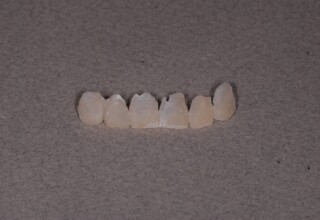

Porcelain Veneers

The best way to solve esthetic problems of the anterior teeth. They combine very little tooth grinding with very high esthetic performance. In the following extensive case anterior teeth presented with: old restorations, staining, poor shape, length and tooth –gingiva ratio. Meticulous diagnostic waxing was performed on study casts and temporary veneers were manufactured. Temporary veneers were used intraorally to evaluate the incorporated changes and to further modify and adjust were needed. When esthetics and function were approved by the patient and were satisfying for the operator the temporaries were used as a guide for the final porcelain veneers. The five final veneers on the upper anterior teeth restored the smile of the patient to almost perfection.

Initial appearance

Final appearance